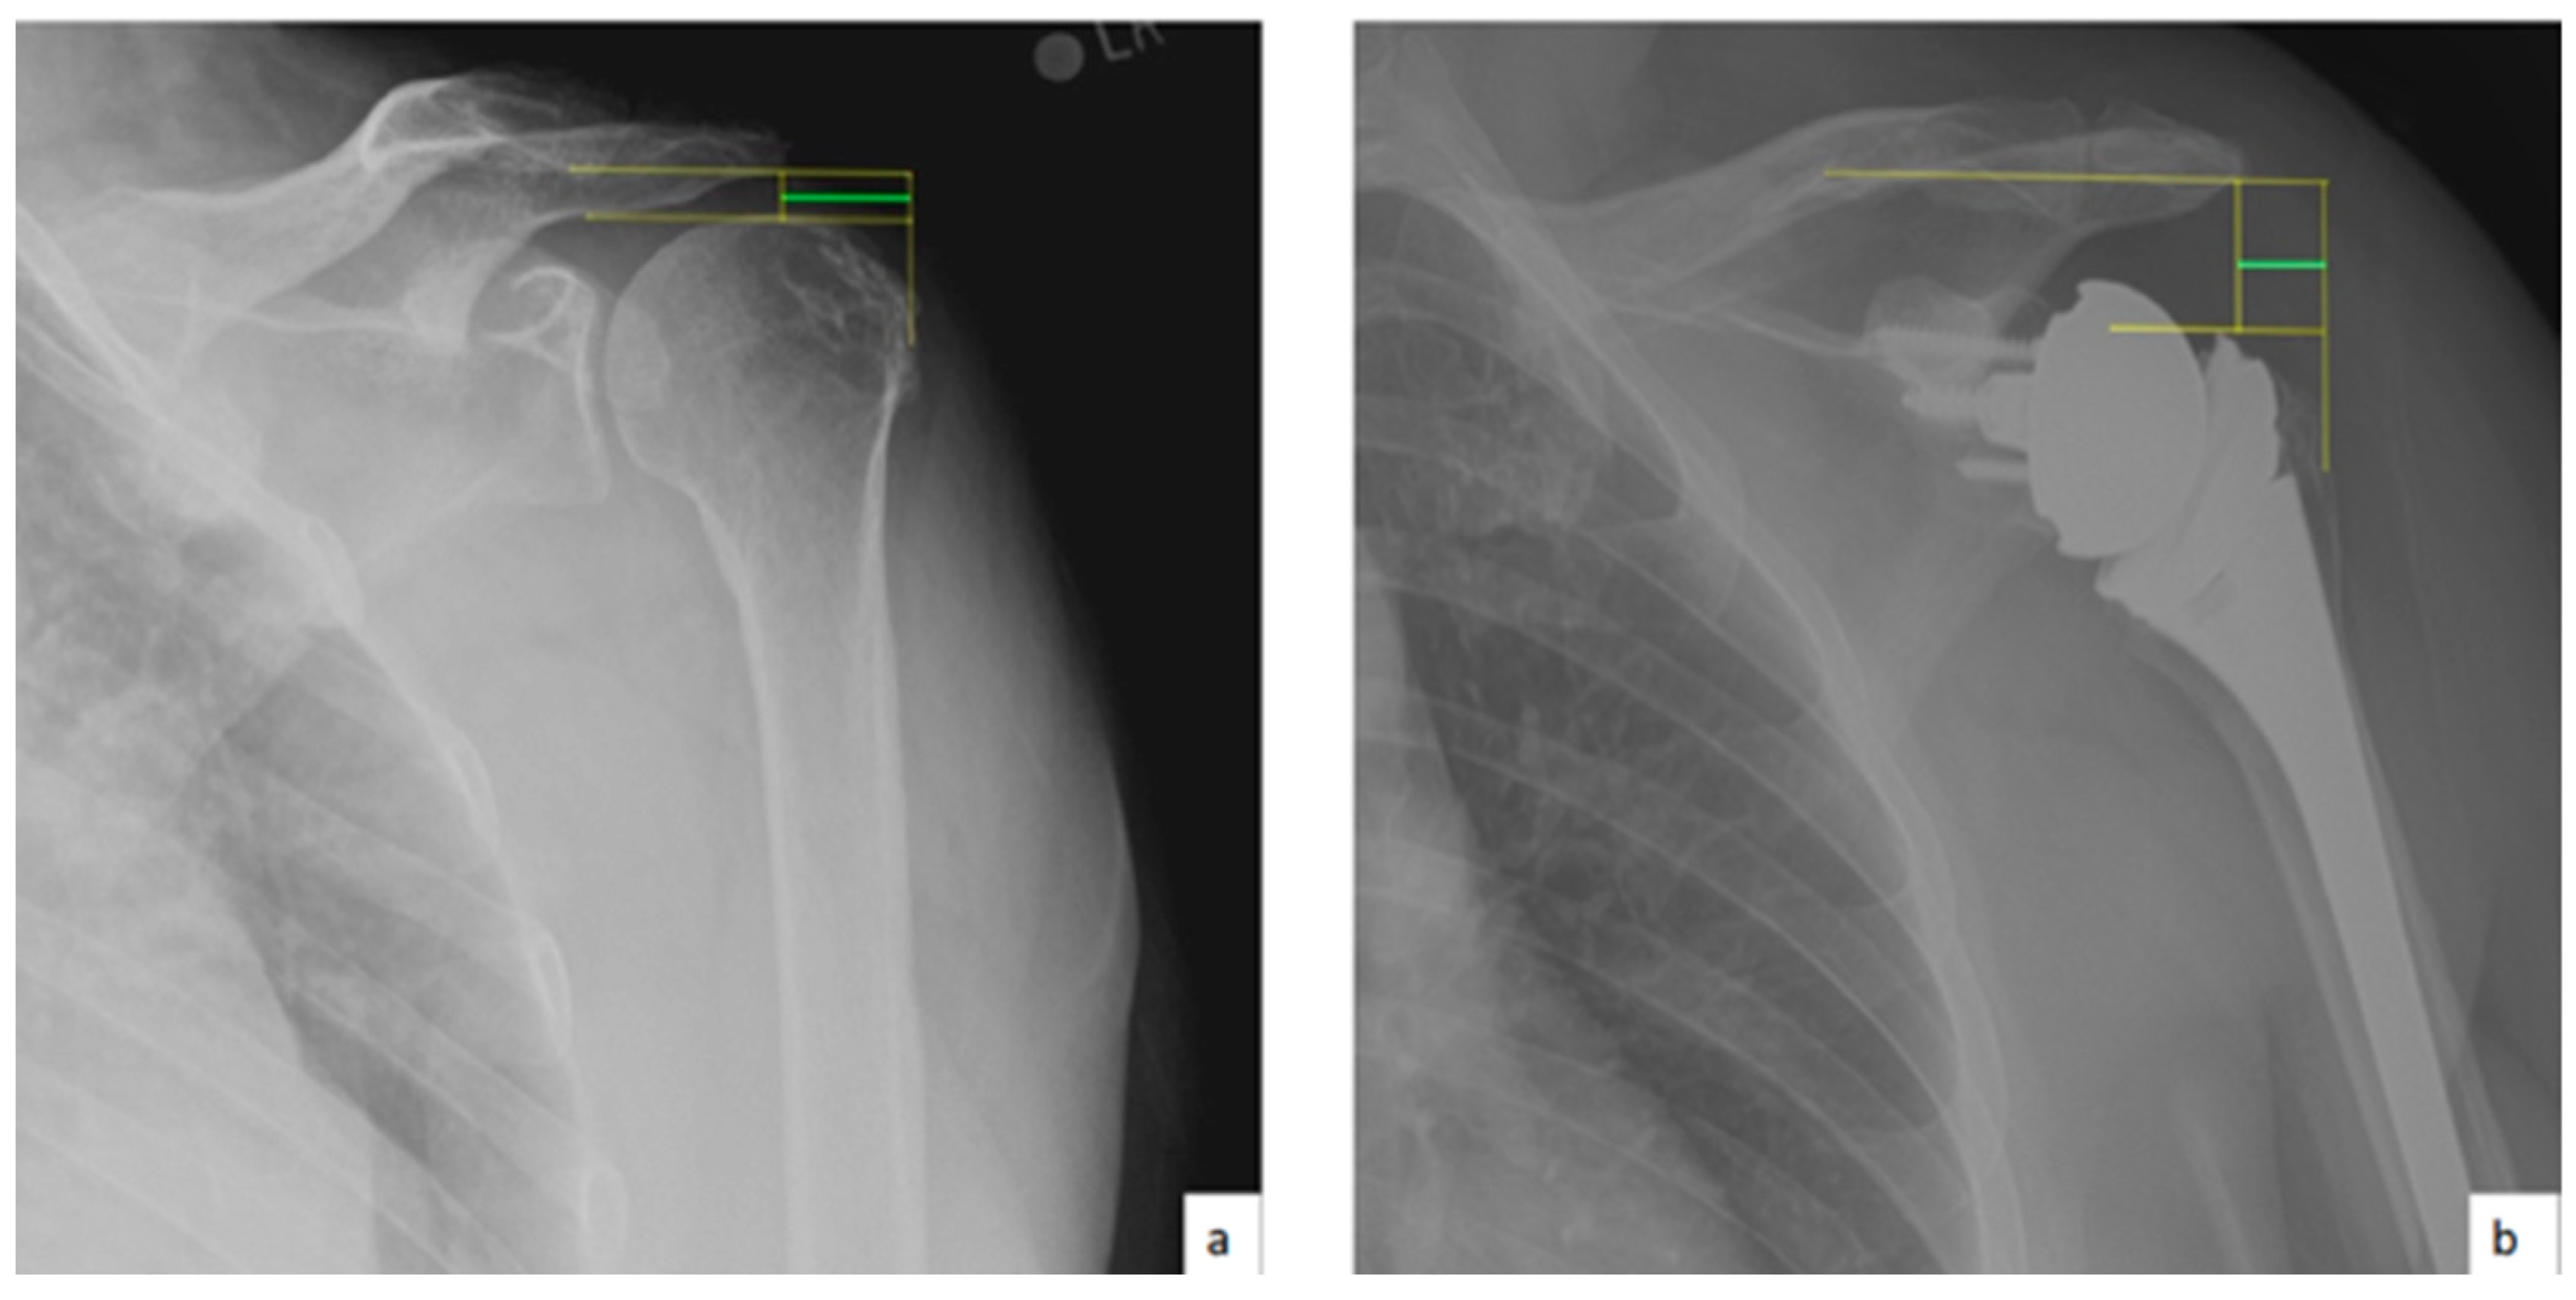

AHD was measured by calculating the perpendicular distance between the most lateral portion of the undersurface of the acromion and a line parallel to the superior border of the greater tuberosity [21] (Figure 1). LHO was measured by determining the distance from the AHD line to the most lateral projection of the greater tuberosity [21] (Figure 2). LSA was measured by drawing a line from the superior glenoid tubercle to the most lateral border of the acromion and a second line from the most lateral border of the acromion to the most lateral border of the greater tuberosity. The angle between these two lines formed the LSA [20] (Figure 3a). DSA was measured by drawing a line between the most lateral border of the acromion and the superior glenoid tubercle and drawing a second line to connect the superior glenoid tubercle with the most superior border of the greater tuberosity. The angle between these two lines formed the DSA [20] (Figure 3b). Glenoid and baseplate were determined as the angle between the floor of the supraspinatus fossa and the glenoid fossa [25] (Figure 4). COR was measured by determining the best fit circle flush to the articular surface, identifying the center of the circle in the humeral head, and then measuring the distance of the perpendicular line between the center of the humeral head and the midpoint of the line connecting the superior and inferior glenoid tubercles [24] (Figure 5b). CSA was measured by a line from the superior pole to the inferior pole of the glenoid and a line from the inferior pole to the lateral edge of the acromion [26] (Figure 5a). In addition, scapular notching was graded according to the Nerot–Sirveaux classification and severity of preoperative cuff tear arthropathy was evaluated according to the Hamada classification [27,28].

Figure 5.

(a) Critical shoulder angle (CSA; green angle); (b) center of rotation (COI; green line).